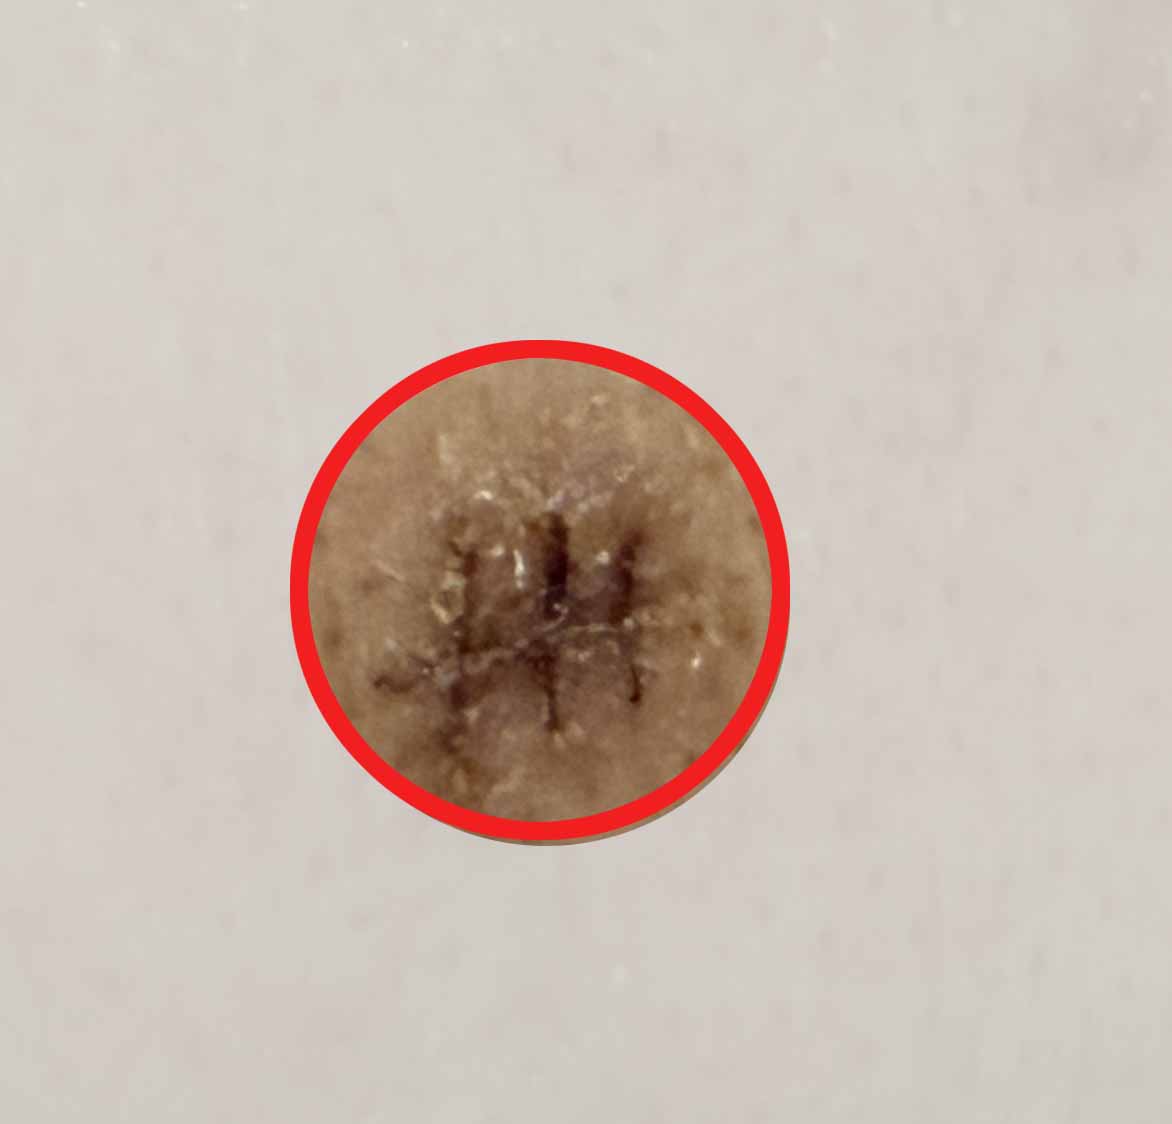

| 🩸 제거된 피지낭종

등에 있던 건 수년간 누적된 상태라 꽤 큰 크기였어요. 안에 딱딱한 피지 찌꺼기와 검은 부분이 있었고, 제거한 조직은 병리 검사에 보냈지만 다행히도 양성 피지낭종이었습니다.

📸 제거된 피지낭종과 수술 부위 사진

※ 아래 더보기 사진은 실제 수술 중 제거된 피지낭종 사진입니다. 불편하신 분은 열람을 삼가 주세요.